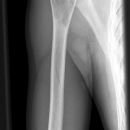

Pseudarthrose